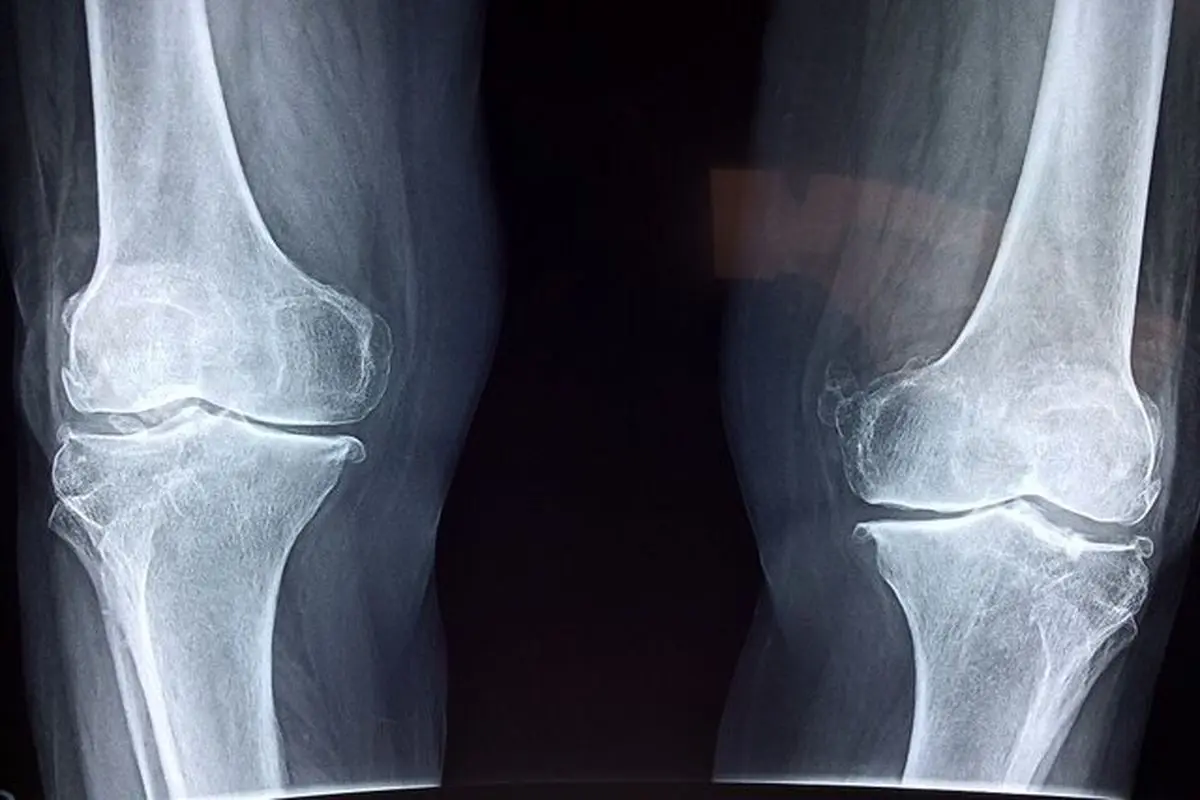

فوق تخصص بیماری‌های روماتولوژی با اشاره به اهمیت پیشگیری و تشخیص زودهنگام پوکی استخوان گفت: این بیماری به کاهش مواد معدنی و آلی در بافت استخوان گفته می‌شود و متأسفانه اصلی‌ترین علامت آن، بی‌علامتی است؛ یعنی در بسیاری از موارد بیمار هیچ نشانه‌ای ندارد و استخوان‌ها به‌تدریج و بی‌صدا دچار ضعف و پوکی می‌شوند، همانند موریانه‌ای که چوب را آهسته می‌خورد.

آذربانی در خصوص روش‌های تشخیص بیماری توضیح داد: تشخیص پوکی استخوان با انجام سنجش تراکم استخوان (BMD) یا دگزا (DEXA) انجام می‌شود. این تست ساده و بدون درد، میزان تراکم مواد معدنی در استخوان را می‌سنجد و با کمترین میزان اشعه انجام می‌شود. حتی در زنان باردار نیز در شرایط خاص قابل انجام است. همه‌ خانم‌های بالای ۶۵ سال و آقایان بالای ۷۰ سال باید بدون هیچ پیش‌شرطی این تست را انجام دهند.

وی در توضیح تفاوت پوکی استخوان با نرمی استخوان افزود: در پوکی استخوان، هم مواد آلی و هم مواد معدنی کاهش می‌یابد، اما در نرمی استخوان عمدتاً مواد معدنی دچار کاهش می‌شوند.